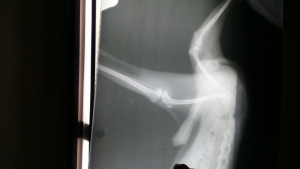

最新个人情况:2020年4.2日右手中指被小狗爪子划出2cm口子,4.3号下午到正规疫苗接种卫生站注射第一针疫苗(广州诺诚)➕破伤风疫苗

不良反应:4.4日凌晨三点高烧冒虚汗,一直烧到第二天下午(4.4号)退为低烧,但是仍然伴有全身性的肌肉疼痛和剧烈头痛,呕吐乏力,手臂红肿,没有食欲,嗜睡,在床上躺了一天一夜,一直到4.5中午,除了体温恢复正常,其它症状依然存在(有些许减弱),但整体可以正常思考了,4.6号上午仍然头疼➕手臂红肿。